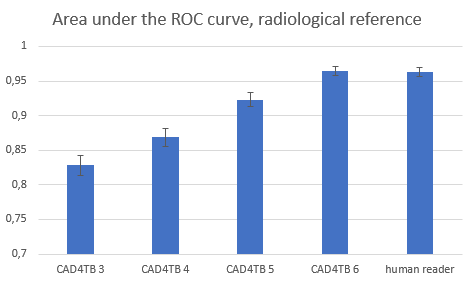

To develop the new version, we have collected a lot more data, from more countries and from a wider variety of X-ray equipment. Our performance tests for CAD4TB 6 were based on an independent validation data set. This data set was not used for training the software. The set had over 7000 images from 10 countries and more than 10 different types of X-ray equipment. All validation images were read independently by two human experts. We have made our image reading process stricter. Because of this stricter reading protocol, the agreement between the human readers is very high. We used one of the readers as the reference standard. This means the verdict of this reader determines if we consider a validation image radiologically abnormal.

Compared to this reference, the second reader achieved a score of 0.963. This score is called the area under the receiver operating characteristics curve and is the internationally accepted standard way of testing software that makes classifications on images. It means that if one randomly takes a normal and an abnormal image from the set of test images, the second reader correctly said which of the two images is the abnormal one in 96.3% of all cases. We tested the new and the earlier versions of CAD4TB against this very high bar. Version 3 of the software, the first version that could process X-rays from different types of machines, achieved a score of 82.8%. This increased with version 4 and 5 to respectively 86.9% and 92.3%. The new version 6, based on deep learning, makes a big step forward and achieves a score of 96.5%, slightly better, but not significantly different, from the second human expert reader.

Figure 1. Performance of the new version of CAD4TB is on par with a human expert reader.